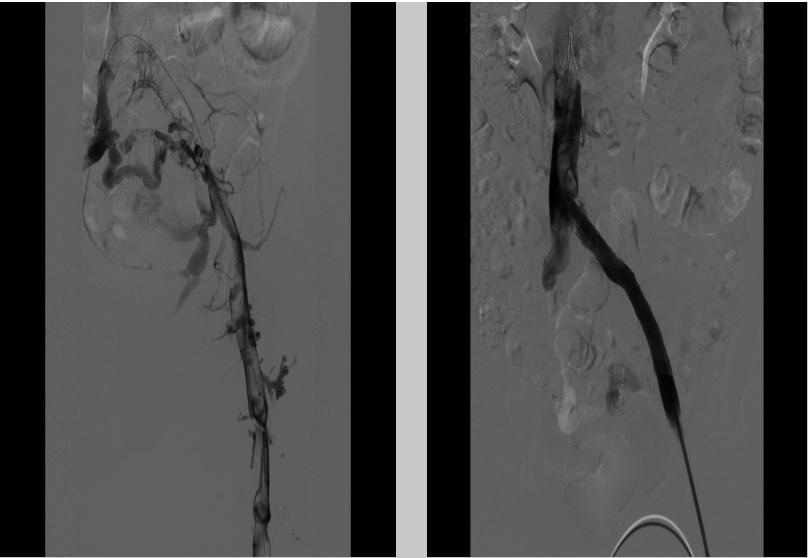

3.静脉血栓性疾病

左下肢深静脉血栓形成